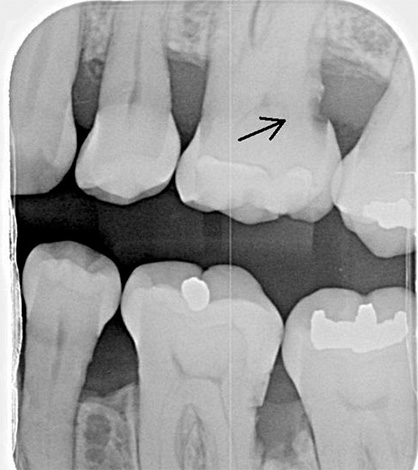

- Esame radiografico. Permette non solo di rilevare cavità subgengivali in un dente sospetto o sotto una corona, ma anche di rivelare i minimi difetti gengivali nell'area delle pareti di contatto strettamente adiacenti l'una all'altra. Allo stesso tempo, anche un leggero "oscuramento" può essere visto nella radiografia del dente, il che indica che i raggi X passano facilmente attraverso il tessuto interessato dalla carie, il che significa che il processo cariato ha già colpito almeno il cemento e al massimo la dentina della radice. Per rilevare la carie nascosta sotto la gomma, viene ampiamente utilizzato un visiografo: un apparato che trasferisce i dati su un computer e consente di identificare un difetto ed esaminarlo in un'immagine ingrandita o con angolazioni diverse.